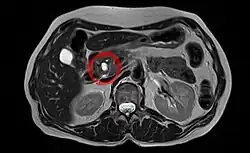

Neoplasia mucinosa papilar intraductal é um tipo de tumor (neoplasia) que se desenvolve nos ductos do pâncreas (intraductal) e caracterizado pela produção de um líquido espesso pelas células do tumor (mucinosa).[1] Caso permaneçam por tratar, podem progredir para cancro invasivo maligno.